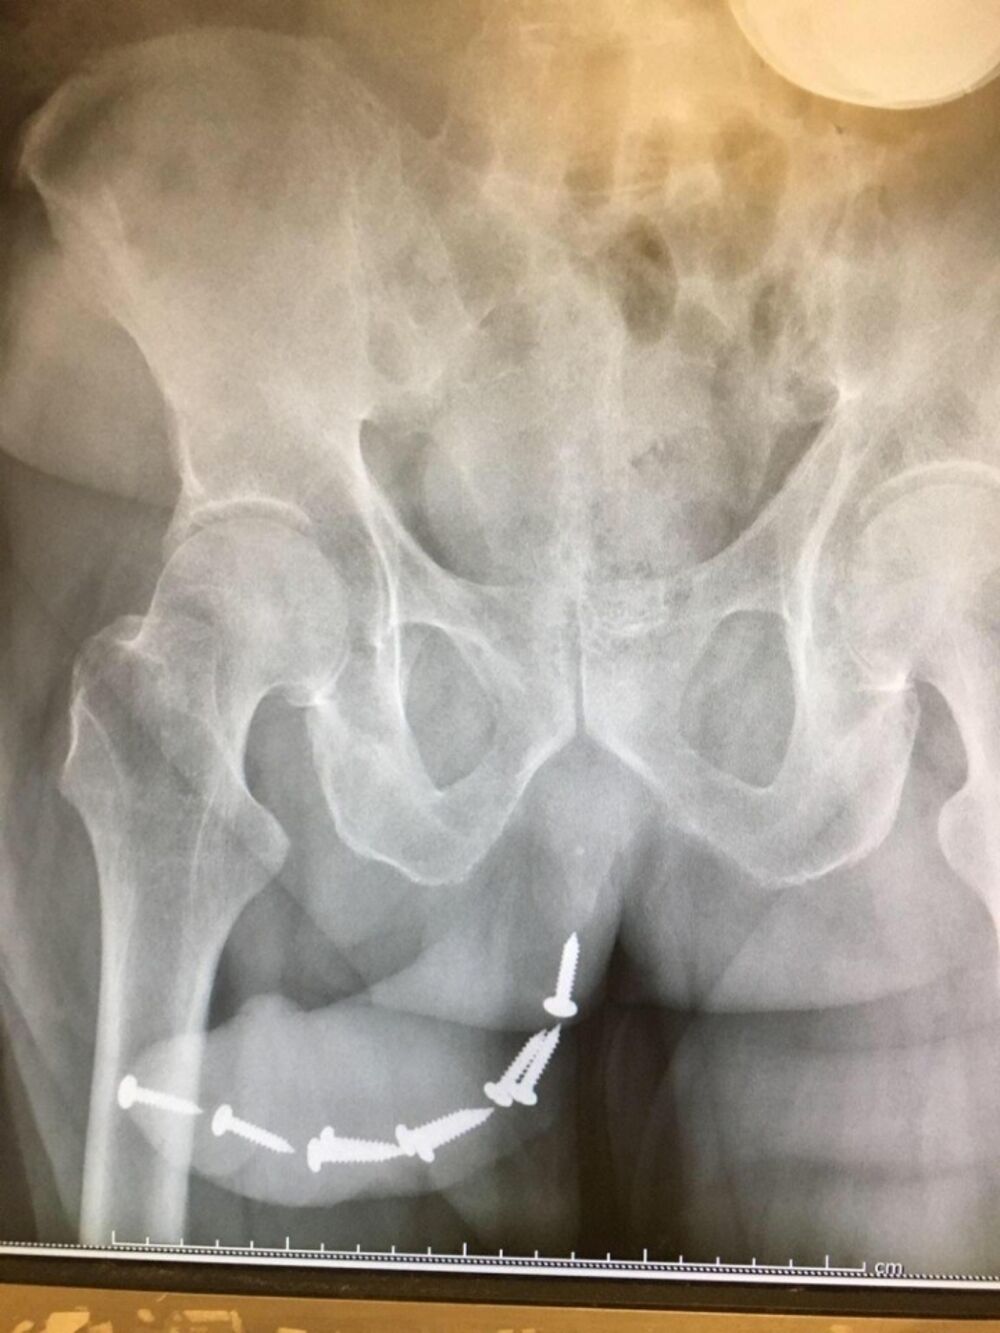

Ukoliko ovaj snimak rendgena nije lažan, malo je reći da je ova devojka preterala u svojoj osveti.